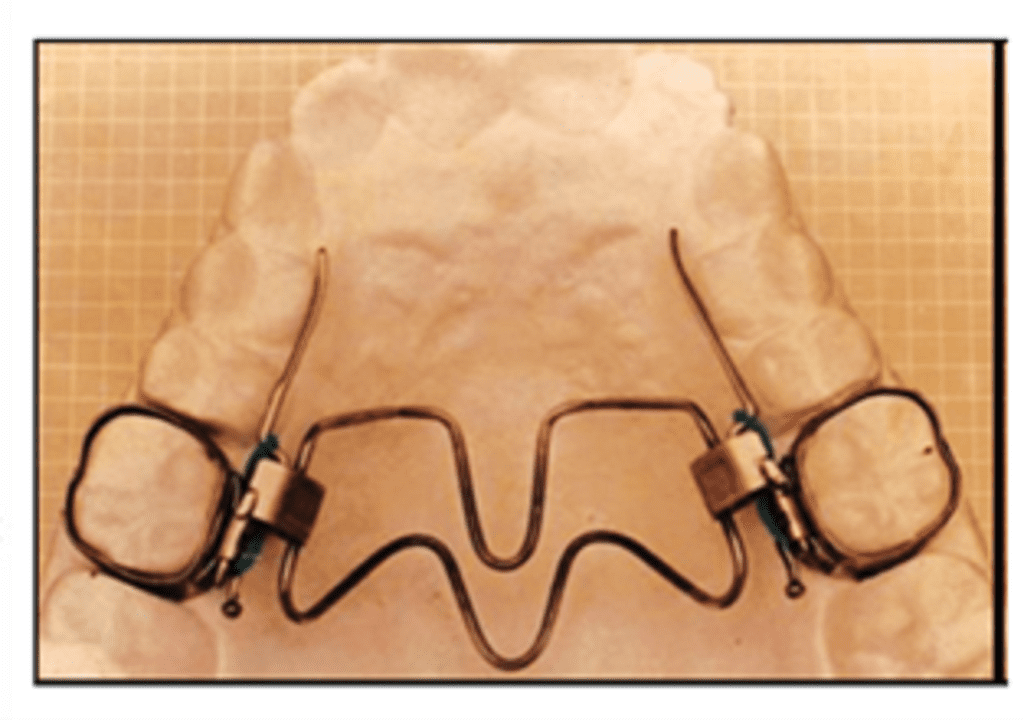

The W-arch appliance was introduced by Ricketts 1975.

Appliance framework Constructed with 0.036-inch stainless steel wire. Wire is adapted to the form of ‘W’ which extends from the first permanent molar to the canine in the anterior palate. Free ends of the ‘W’ are adapted closely to the palatal surfaces of premolars/deciduous molars. Appliances should be away from the palatal mucosa to prevent tissue irritation. Lingual arch is soldered to bands on molars. The finished appliance is cemented to the first permanent molars.

Activation

- For anterior expansion – opening of apices of ‘W’ (position 2)

- For posterior expansion – opening near anterior region (position 1)

The appliance delivers proper force levels if opened 4–5 mm wider than the passive width and should be adjusted to this dimension before being inserted. The appliance is activated at the rate of 2mm per month until the cross bite is mildly overcorrected.